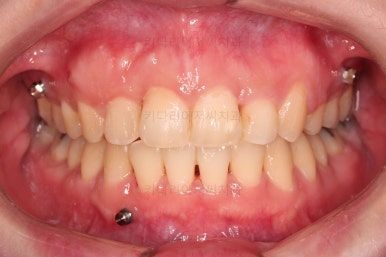

초진 시 입안의 모습입니다.

앞니쪽이 조금 삐뚤어 보인다는 점 이외에는 큰 문제점이 보이지 않죠?

어금니쪽을 자세히 관찰해 보면, 위아래 어금니의 맞물림(교합)이 어긋나 있는데요.

톱니바퀴처럼 물려야 되는 교합이 한 칸 씩 윗니가 아랫니보다 앞으로 나가있는 앵글씨 2급 부정교합 상태였습니다.

치료 종료 시 입안의 모습입니다.

윗니만 발치를 했지만 교합이 잘 맞고요.

한 쪽 송곳니가 없지만 기능적으로 전혀 문제를 못느끼실 교합을 맞춰놨고요.

위아랫니 가지런해졌고요.

대신 중앙선은 약간 틀어져 있는데요.

한 쪽은 송곳니가 없고 한 쪽은 작은 어금니를 발치했기 때문인데요.

18개월이라는 짧은 기간동안 부정교합, 덧니, 심지어 매복치아까지 개선했는데 양측 치아 사이즈 문제로 생기는 중앙선 정도는 아무 문제가 안되는거죠.

전후 비교입니다.